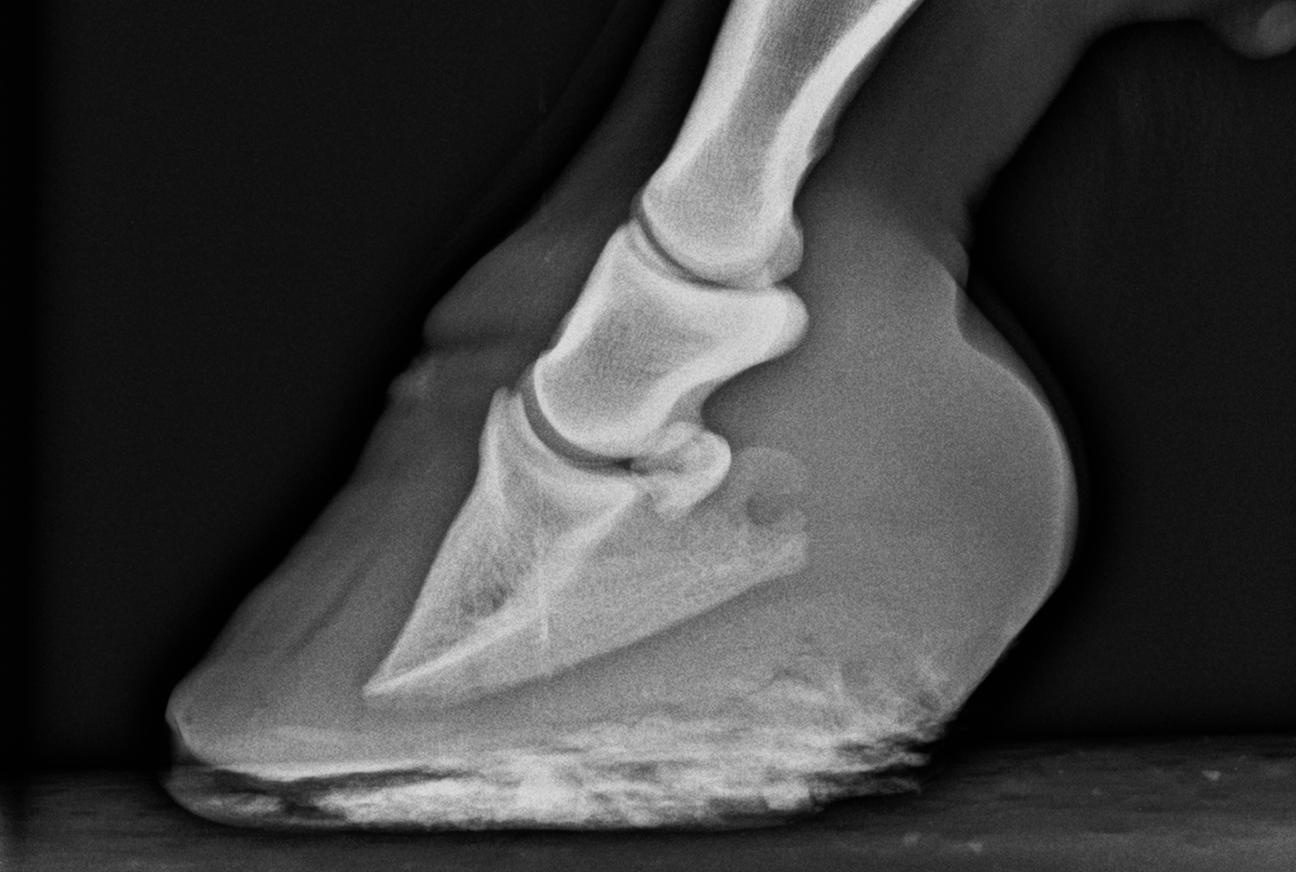

Röntgenundersökningar

Röntgenundersökningar utföres i samband med hältundersökningar, besiktningar och vid sk friröntgen av unga hästar. Röntgen av halskotpelare och rygg vid ryggproblem samt av skalle och tandrötter vid misstanke om bihålesjukdom respektive tandproblem. Självklart kan det bli aktuellt att även röntga en sårskada eller en märklig knöl på ett ben.